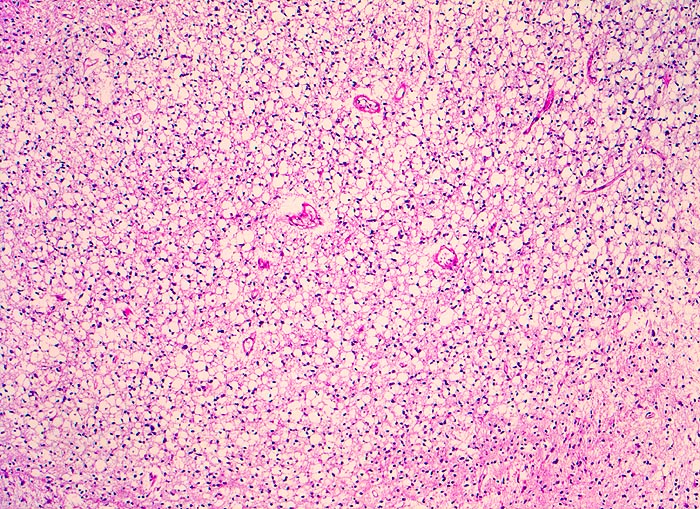

PathoPic ID 5255 - Oligodendrogliom (WHO Grad II)

Oligodendrogliom (WHO Grad II)

maligner Tumor

Hirn frontal

Nervensystem

Tumorzellen mit kleinen Kernen umgeben von einem Halo (Fixationsartefakt)

Kopfschmerzen und epileptische Anfälle seit zwei Jahren.

Histologie

50